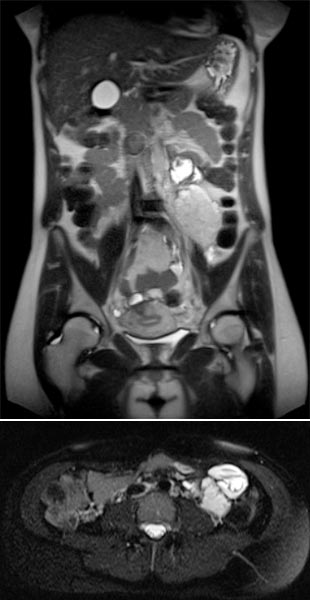

Coronal and axial T2-weighted HASTE sequences without contrast 8 weeks after delivery. Postpartum, there is again a marked reduction in the size of the venous malformation.

In the 21st gestational week, there has been an increase in size of the intra-abdominal venous malformation due to hormone stimulation during pregnancy. Despite the increase in size, there was no displacement of the placenta. Another follow-up was planned approximately 3-4 weeks before delivery. This is relevant in order to avoid possible obstetric complications and to avoid intraprocedural bleeding complications in the event of a cesarean section becoming necessary. However, the patient already had to deliver in the 35th week due to preterm labor. A repeat MRI could not be performed in time. An uncomplicated spontaneous delivery occurred.

The venous malformation showed a clear size decrease 8 weeks after delivery, so that minimally invasive treatment by sclerotherapy is currently not necessary for the nursing mother. The large venous malformation was asymptomatic at this time.